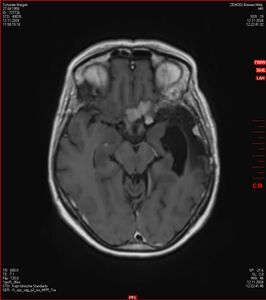

MRT vom 12. November 2024

So nun ein paar neue Bilder aus meinem Kopf. (Durch klicken bekommt man eine größe Ansicht eines Einzelbildes).

Die letzten drei Bilder Zeigen aus meiner Sicht den Tumor, der im Jahr 2021 bestrahlt wurde.

Zum Vergleich nun auch die Bilder vom 1.12.2023: